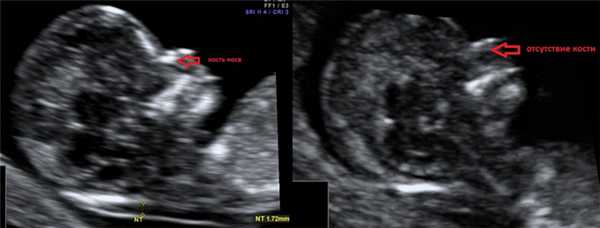

2. Гипоплазия\аплазия костей носа.

Гипоплазия костей носа - уменьшение размеров косточки носа в зависимости от КТР вашего малыша.

Аплазия костей носа - отсутствие визуализации косточки носа у вашего малыша.

Отсутствие видимости костной части спинки носа у плода или ее недоразвитие (недостаточно яркая) на первом скрининге связана с задержкой отложения кальция. Такая ситуация несколько чаще может встречаться у плодов с синдромом Дауна, однако важно, что:

- само по себе отсутствие костей носа на УЗИ не является аномалией развития; может встречаться у абсолютно здоровых плодов (в 3% случаев);

- для оценки степени индивидуального риска необходима оценка остальных ультразвуковых маркеров (толщина воротникового пространства плода, показатели кровотока на сердечном клапане, показатели кровотока в венозном протоке, ЧСС плода) и биохимического анализа материнской сыворотки (РАРР-А, ХГЧ);